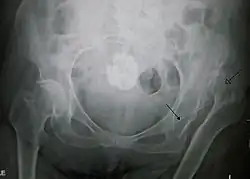

| X-ray showing a joint dislocation of the left hip. | |

Typically, people with hip dislocations present with severe pain and an inability to move the affected leg.[1][4] Diagnosis is made by physical exam and plain X-rays of the hips. A CT scan is recommended following reduction to rule out complications. Complications include osteonecrosis, femoral head fractures, and posttraumatic osteoarthritis.[12][13]

An anterior-posterior (AP) X-ray of the pelvis and a cross-table lateral X-ray[24] of the effected hip are ordered for diagnosis.[4][5][16] The size of the head of the femur is then compared across both sides of the pelvis. The affected femoral head will appear larger if the dislocation is anterior, and smaller if posterior.[7] A CT scan may also be ordered to clarify the fracture pattern.[20]